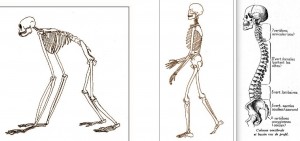

Tout a commencé lorsque quelques uns de nos cousins de la famille des Anthropoïdes se sont décidés à se dresser sur leurs pattes de derrière. Auparavant, leurs ancêtres se déplaçaient soit dans les ramées des grands arbres où ils vivaient, comme aujourd’hui les orangs outangs, soit pour d’autres, plutôt terriens, à quatre pattes tels les chimpanzés en s’appuyant sur leurs doigts. Et puis voici qu’il y a quelques millions d’années quelques uns d’entre eux des uns et/ou des autres se sont dressés et sont devenus bipèdes. D’évidence ce fut une réussite, et nous aurions tord de nous en plaindre. Mais les transformations anatomiques qui ont suivi ressemblent plus à un itinéraire bison futé qu’à une droite ligne. Membres et ceintures les soutenant se sont transformés, mais c’est en particulier l’épine dorsale qui a été redessinée pour assurer dans un port vertical le soutien de la tête, et aussi plus bas celui des principaux organes viscéraux. Cette érection de tout un corps a eu pour conséquence que la colonne vertébrale adopte un nouveau design, et de courbe, elle est devenue sinueuse, comme illustré ici.

Celle-ci est la courbure primordiale pour l’équilibration du tronc : en effet, même s’il se verticalise, le sacrum humain reste oblique et orienté vers le haut et l’avant. De sorte qu’une courbure en creux vers l’arrière, et en bas de la colonne est obligatoire pour ramener facilement le centre de gravité du tronc au dessus du polygone de sustentation (la surface entre les points de contacts au sol). Sans cette courbure basse, il faut déformer vers l’arrière tout le reste de la colonne et ramener les épaules en arrière avec une force maintenue, comme les singes qui se tiennent debout. Cette position est à la fois compliqué sur le terme de l’équilibre et de la locomotion et peu efficient sur la dépense énergétique.